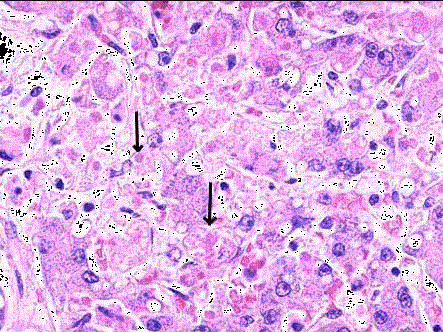

问题 肝穿刺送检标本,镜下如图所示,箭头所指肝细胞出现何种病变 ( )

选项 A.细胞水肿 B.脂肪变性 C.玻璃样变性 D.嗜酸性变 E.点状坏死

答案 D